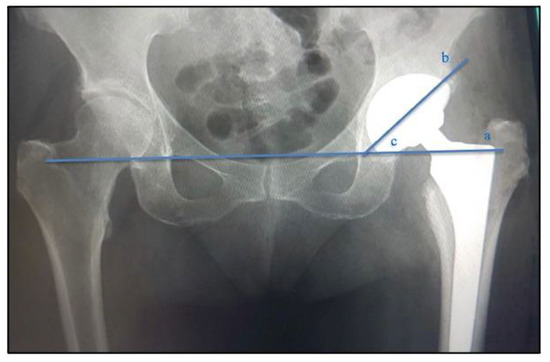

2.3. Analysis of Radiographic Parameters: Positioning and Inclinations of the Acetabular Component